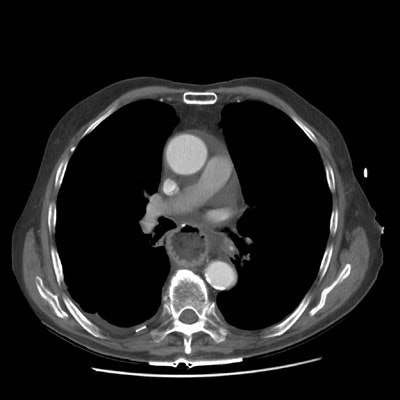

Pericardial effusion:

The exam below demonstrates a low density pericardial fluid collection. The effusion can be seen to extend into the pericardial recesses anterior to the ascedning aorta and the area posterior to the pulmonary outflow tract (anterior to the left upper lobe pulmonary vein). The patient has had a prior gastric pull-through procedure.